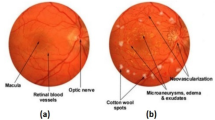

Diabetic retinopathy (DR) is one of the most common consequences of diabetes. It affects the retina, causing blood vessel damage which can lead to loss of vision. Saving patients from losing their sight or at least slowing the progress of this disease depends mainly on the early detection of this pathology, on top of the detection of its specific stage. Furthermore, the early detection of diabetic retinopathy and the follow-up of the patient’s condition remains an arduous task, whether for an experienced expert ophthalmologist or a computer-aided diagnosis technician. In this paper, we aim to propose a new automatic diabetic retinopathy severity level detection method. The proposed approach merges the pyramid hierarchy of the discrete wavelet transform of the retina fundus image with the modified capsule network and the modified inception block proposed, in addition to a new deep hybrid model that concatenates the inception block with capsule networks. The performance of our proposed approach has been validated on the APTOS dataset, as it achieved a high training accuracy of 97.71% and a high testing accuracy score of 86.54%, which is considered one of the best scores achieved in this field using the same dataset.